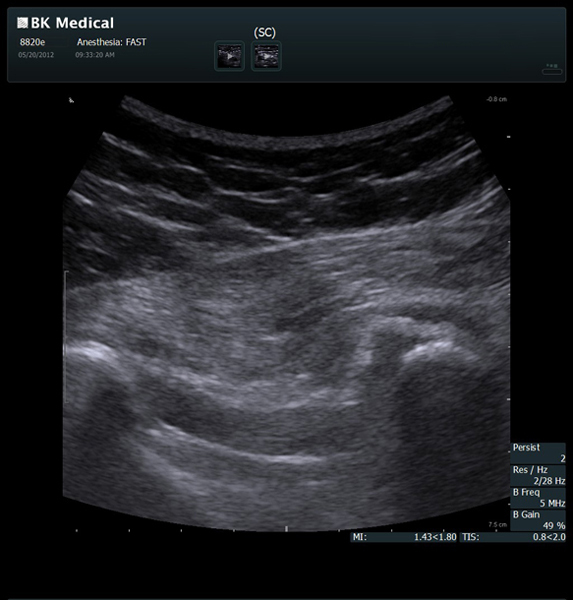

Transducers Designed for Guidance

BK Medical offers high-frequency linear transducers, imaging from 18-2 MHz for upper and lower extremities, and curved array abdominal transducer 8820e for special deep nerves or paravertebral/spinal applications. Our transducers provide superb detail that makes it easy to see your needle during procedures.